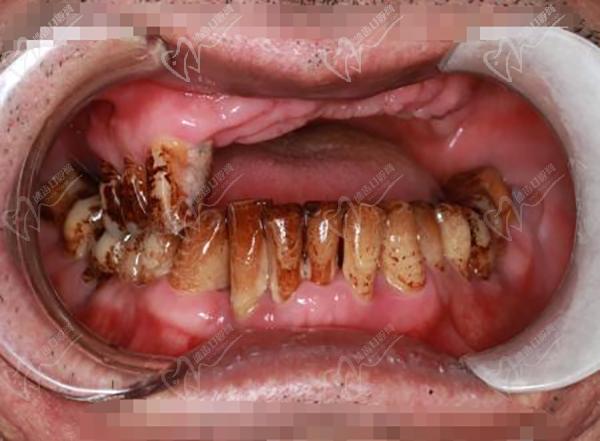

7、廣州暨博口腔醫(yī)院(體育東店):專注口腔醫(yī)療20余年,在牙齒美白、全口種植等方面技術嫻熟。